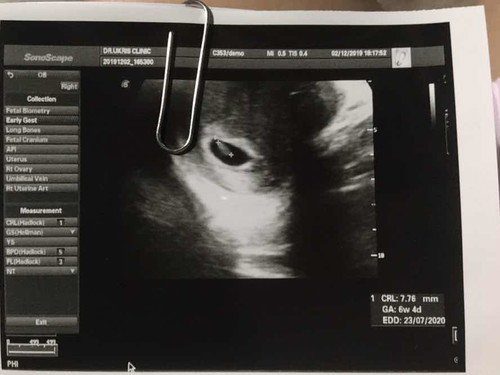

วันแรกของการไปฝากท้อง

ตอนแรกลังเลมากคิดว่าตัวเองท้องจริงรึ่ป่าวซื้อที่ตรวจมาตรวจ5 อัน สรุปท้องจ้า ❤️?